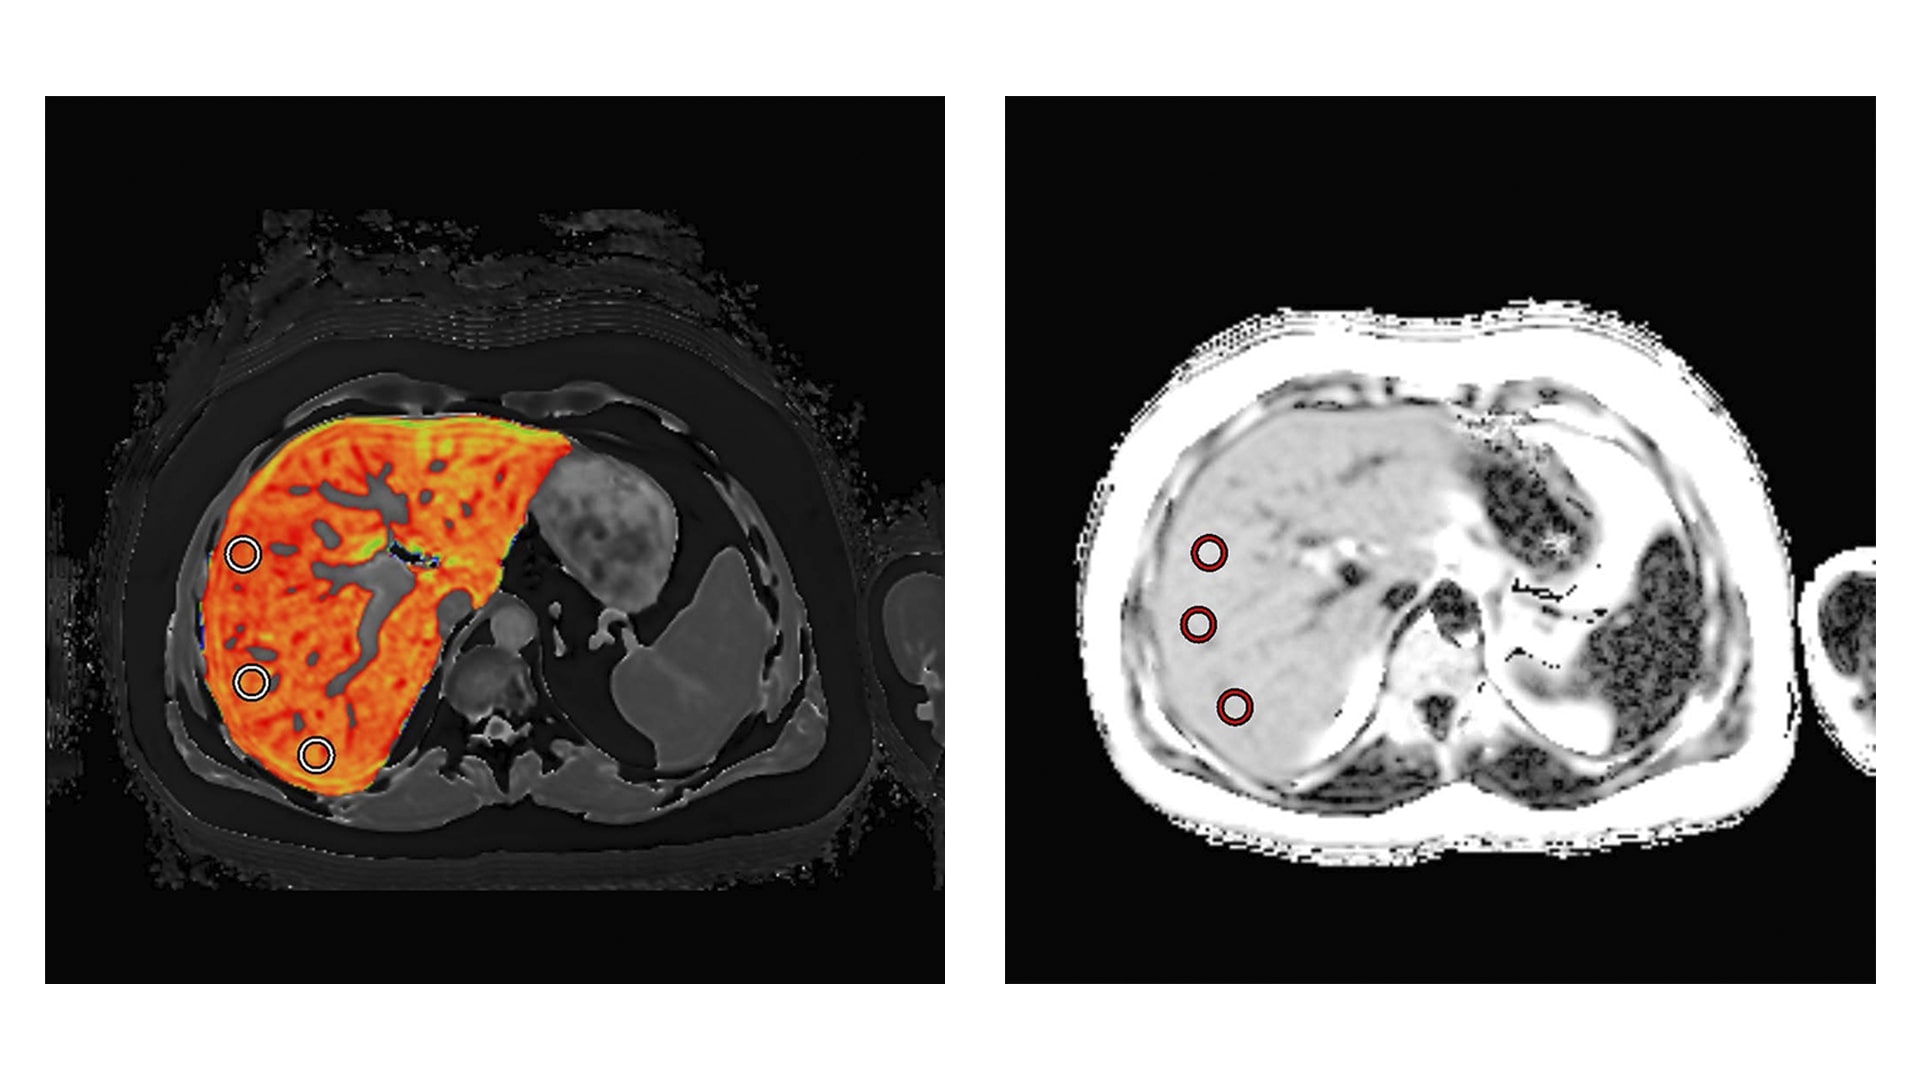

These funds have been awarded under the Drug Development Tool Research Grant (U01). The study will qualify the imaging markers cT1 and PDFF as drug development tools in non-alcoholic steatohepatitis (NASH); initially as diagnostic screening biomarkers to identify patients for inclusion in NASH clinical trials, then as pharmacodynamic efficacy biomarkers to detect clinically meaningful change, with the ultimate objective being approval as non-invasive surrogate endpoints. LiverMultiScan will help identify patients for NASH clinical trials. In discriminating healthy volunteers and patients with no fibrosis on liver biopsy from those with any degree of fibrosis (Ishak ⩾ F1), cT1 had a sensitivity of 86% and a specificity of 93% at a threshold of 800ms. (Journal of Hepatology, 2014, 60(1), 69 – 77).

“Non-alcoholic fatty liver disease is the most common form of chronic liver disease globally. Patients with the aggressive form of fatty liver called fibrotic non-alcoholic steatohepatitis (fibrotic NASH) have the highest risk of progression to cirrhosis and end-stage liver disease. Identifying these patients and assessing their response to different therapeutic agents represents the highest unmet need. LiverMultiScan is an attractive non-invasive method to address this unmet need. The grant will allow the Texas Liver Institute (TLI), a tertiary referral center for patients with liver disease, to collaborate with Perspectum to validate the use of LiverMultiScan in identifying patients with fibrotic NASH that will benefit from therapeutic interventions“. – Dr. Naim Alkhouri, the Texas Liver Institute

“Cases in this study will be patients who would typically qualify for randomization in a clinical trial comparing treatments for non-alcoholic steatohepatitis with fibrosis. Controls will be patients who were thought to possibly have NASH with fibrosis, but whose biopsies showed less severe or no disease. We hope to show that our imaging biomarkers can effectively discriminate cases from controls.” – David DeBrota, MD, VP of Medical R&D, Perspectum